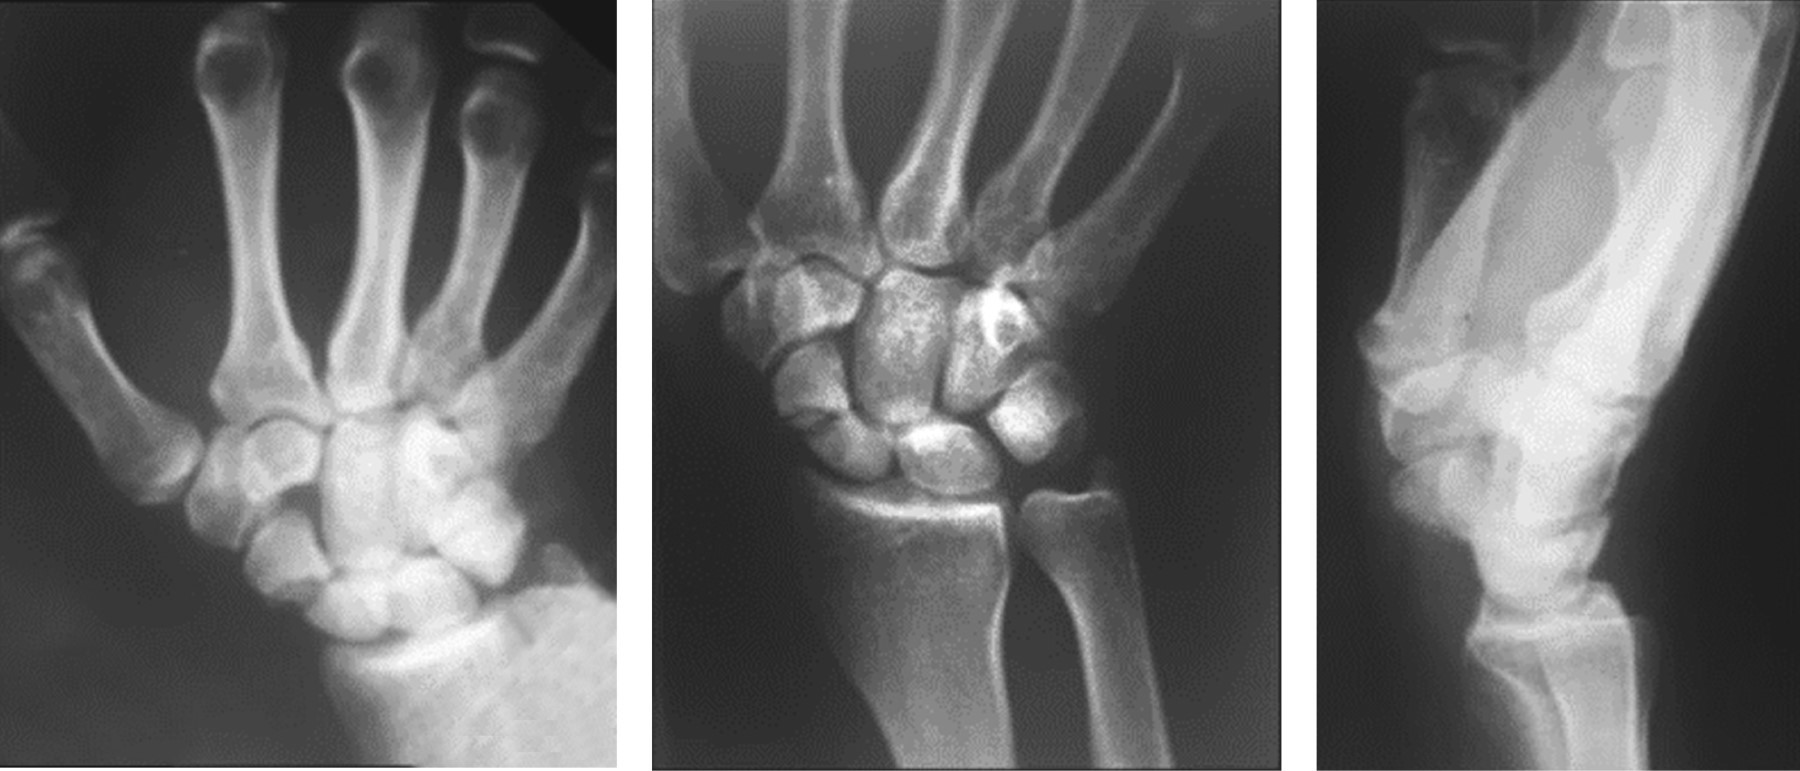

A 28-year-old right-handed male, with no comorbidities, sustained a wrist injury when he fell from his own height and landed with an outstretched right hand. He evolved with swelling, limitation of movement, and tenderness on palpation in his anatomical snuff box. He was initially assessed in another institution where through plain radiographs the diagnosis of scaphoid fracture was made. It was classified as a Herbert and Fischer type B2 (complete displaced scaphoid waist fracture) (Figure 1). Consequently, he was immobilized with a below-elbow cast without the inclusion of the proximal phalanx of the thumb. After three weeks, the patient removed his cast and decided to abandon the treatment and medical follow-up. At seven months he consulted again for pain. Once more, posteroanterior, lateral, and scaphoid (30° wrist extension, 20° ulnar deviation) plain radiographs of the wrist were requested (Figure 2). The fracture exhibited absence of consolidation. Due to the evolution time (more than six months from the initial trauma), a scaphoid nonunion was diagnosed. A CT scan was requested to assess displacement. This revealed a Herbert type D nonunion (established nonunion), with no density alteration in the scaphoid fragments and no displacement (Figure 3). According to the Slade and Geissler classification, it was a grade II nonunion, with no sclerosis, no bone cysts, and a small resorption edge. Surgical treatment was indicated, but the patient refused. Then he returned to our institution 10 months after the initial injury. He presented with pain in the anatomical snuffbox, on axial compression of the first metacarpal, and on palpation of the scaphoid tubercle. Mobility was similar to the contralateral side but painful (visual analogue scale [VAS] 7/10) (Table 1). Surgical treatment was once more indicated. The patient was then lost in follow-up and returned to control 15 months after the initial injury without having undergone any type of treatment or immobilization. He showed a spontaneous clinical improvement, a complete absence of pain (VAS 0/10) and range of motion, and grip strength similar to the healthy contralateral side (Table 1). Plain radiographs and CT scan with 3D reconstruction were requested. The new images showed scaphoid consolidation (Figures 4 and 5).

Figure 1

Figure 2